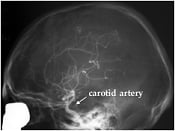

X-ray examination of brain vessels using the method – cerebral angiography – introduced by Moniz. A radio-opaque contrast medium has been injected into one of four neck vessels (carotid artery) supplying the brain. Normal case (left). A case of vascular malformation situated in the parietal (mid superior) part of the brain and fed by an enlarged artery (right).

Cerebral angiography – an X-ray investigation of the blood vessels of the brain. The blood vessels are made visible by injecting a dye that is opaque to X-rays.